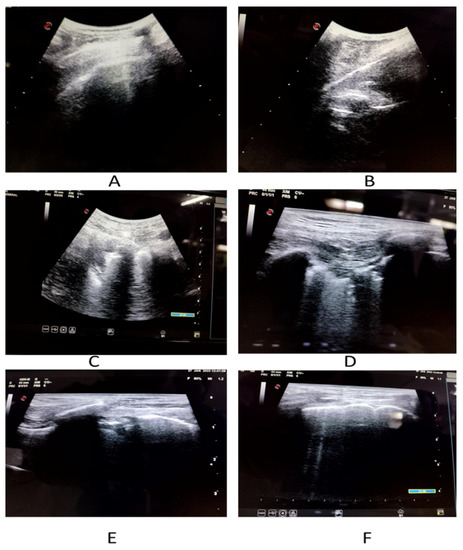

| Lung ultrasonography (n = 152) | |||

| COVID-19 suggestive | 120 (78.95) | ||

| Right pleural effusion | 24 (15.79) | ||

| Left pleural effusion | 21 (13.82) | ||

| Pericardial effusion | 39 (25.66) | ||

| Lung score, (Mean ± SD) | 11.6 ± 4.3 | ||

| Affected Zone | IP/IBL | CBL | C |

| 1 (right upper anterior) | 27 | 12 | 24 |

| 2 (right lower anterior) | 36 | 27 | 9 |

| 3 (right upper lateral) | 30 | 30 | 12 |

| 4 (right lower lateral) | 42 | 30 | 9 |

| 5 (left upper anterior) | 33 | 12 | 18 |

| 6 (left lower anterior) | 27 | 12 | 15 |

| 7 (left upper lateral) | 24 | 24 | 18 |

| 8 (left lower lateral) | 39 | 27 | 6 |

| 9 (right upper posterior) | 24 | 18 | 27 |

| 10 (right lower posterior) | 39 | 15 | 57 |

| 11 (left upper posterior) | 21 | 15 | 18 |

| 12 (left lower posterior) | 39 | 15 | 54 |